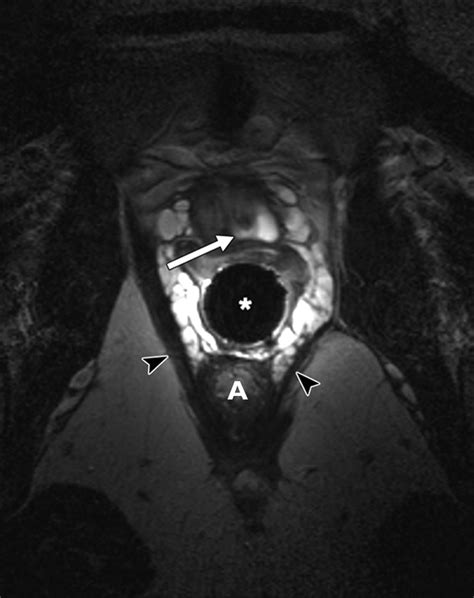

MRI (Magnetic Resonance Imaging) The gold standard for visualizing the size and location of the diverticulum.

Diagnostic Procedures

Diagnosis requires a high index of suspicion, especially when standard treatments for UTIs fail. A physician will typically perform a physical exam, which may reveal a tender mass along the anterior vaginal wall. If pressure is applied to the mass, it is not uncommon for a small amount of urine or purulent discharge to exit the urethra.